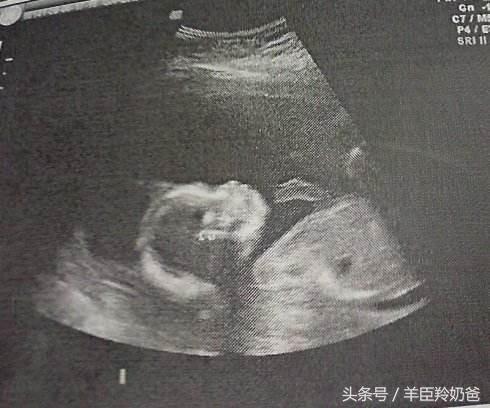

2、孕中期20-24周

这个时期是做B超的最合适的时间,也是最重要的一次检查,在这个阶段可以通过B超检查胎儿的发育情况、能检查出胎儿是否有畸形,对胎儿的位置和羊水量也有一定的了解。